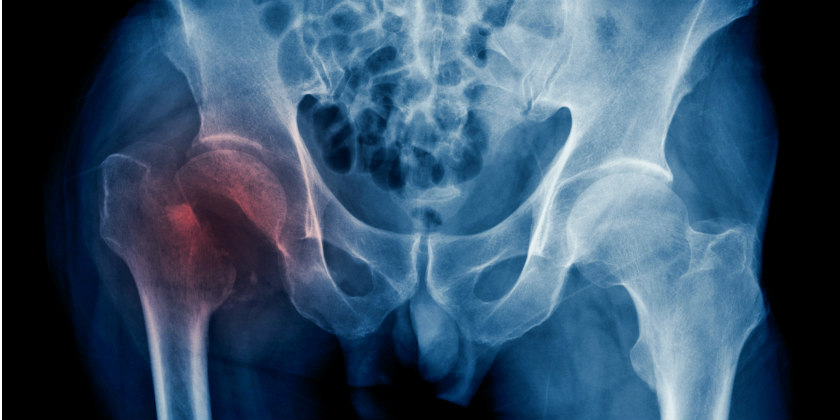

Una fractura es la ruptura total o parcial de un hueso, no importa el hueso su denominación será la misma. Esto ocurre cuando se aplica una gran cantidad de presión sobre el hueso, hasta el punto en el que este se parte. En este tipo de lesiones es necesaria la intervención quirúrgica para la reparación del hueso, aunque esto no ocurre en todos los casos.

Las fracturas pueden ocurrir por diversas causas, aunque lo más común es que ocurra por algún accidente, una caída o alguna lesión causada durante una actividad física. Aunque en algunos casos puede ocurrir una fractura por desgaste, la cual es la aplicación prolongada o constante de presión, hasta que el hueso finalmente colapsa y se rompe.

Síntomas de una fractura

Si bien esta lesión tiene distintos tipos, generalmente suele presentar el mismo patrón de síntomas sin importar la clase de fractura que se presente:

- La extremidad o la articulación lesionada se encuentra visiblemente fuera de lugar o tiene un aspecto deformado.

- Dolor intenso.

- Hinchazón o hematomas.